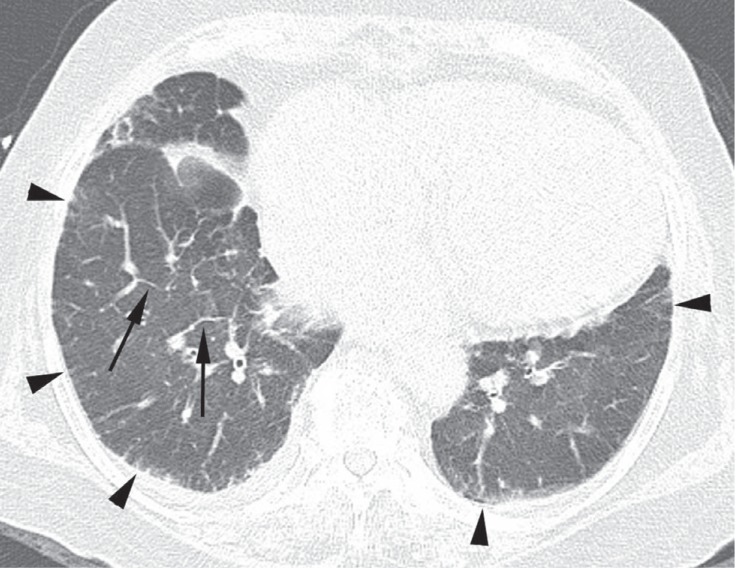

Figure 2

A 62-year-old female with amiodarone pulmonary toxicity (APT) exhibiting an organizing pneumonia pattern. A computed tomography (CT) scan obtained at the level of both upper lobes revealed bilateral patchy consolidations and ground-glass opacities. Also noted were small bilateral pleural effusions. The APT CT score was 6, and the involved regions included the right and left upper lungs in the central, middle, and peripheral regions.